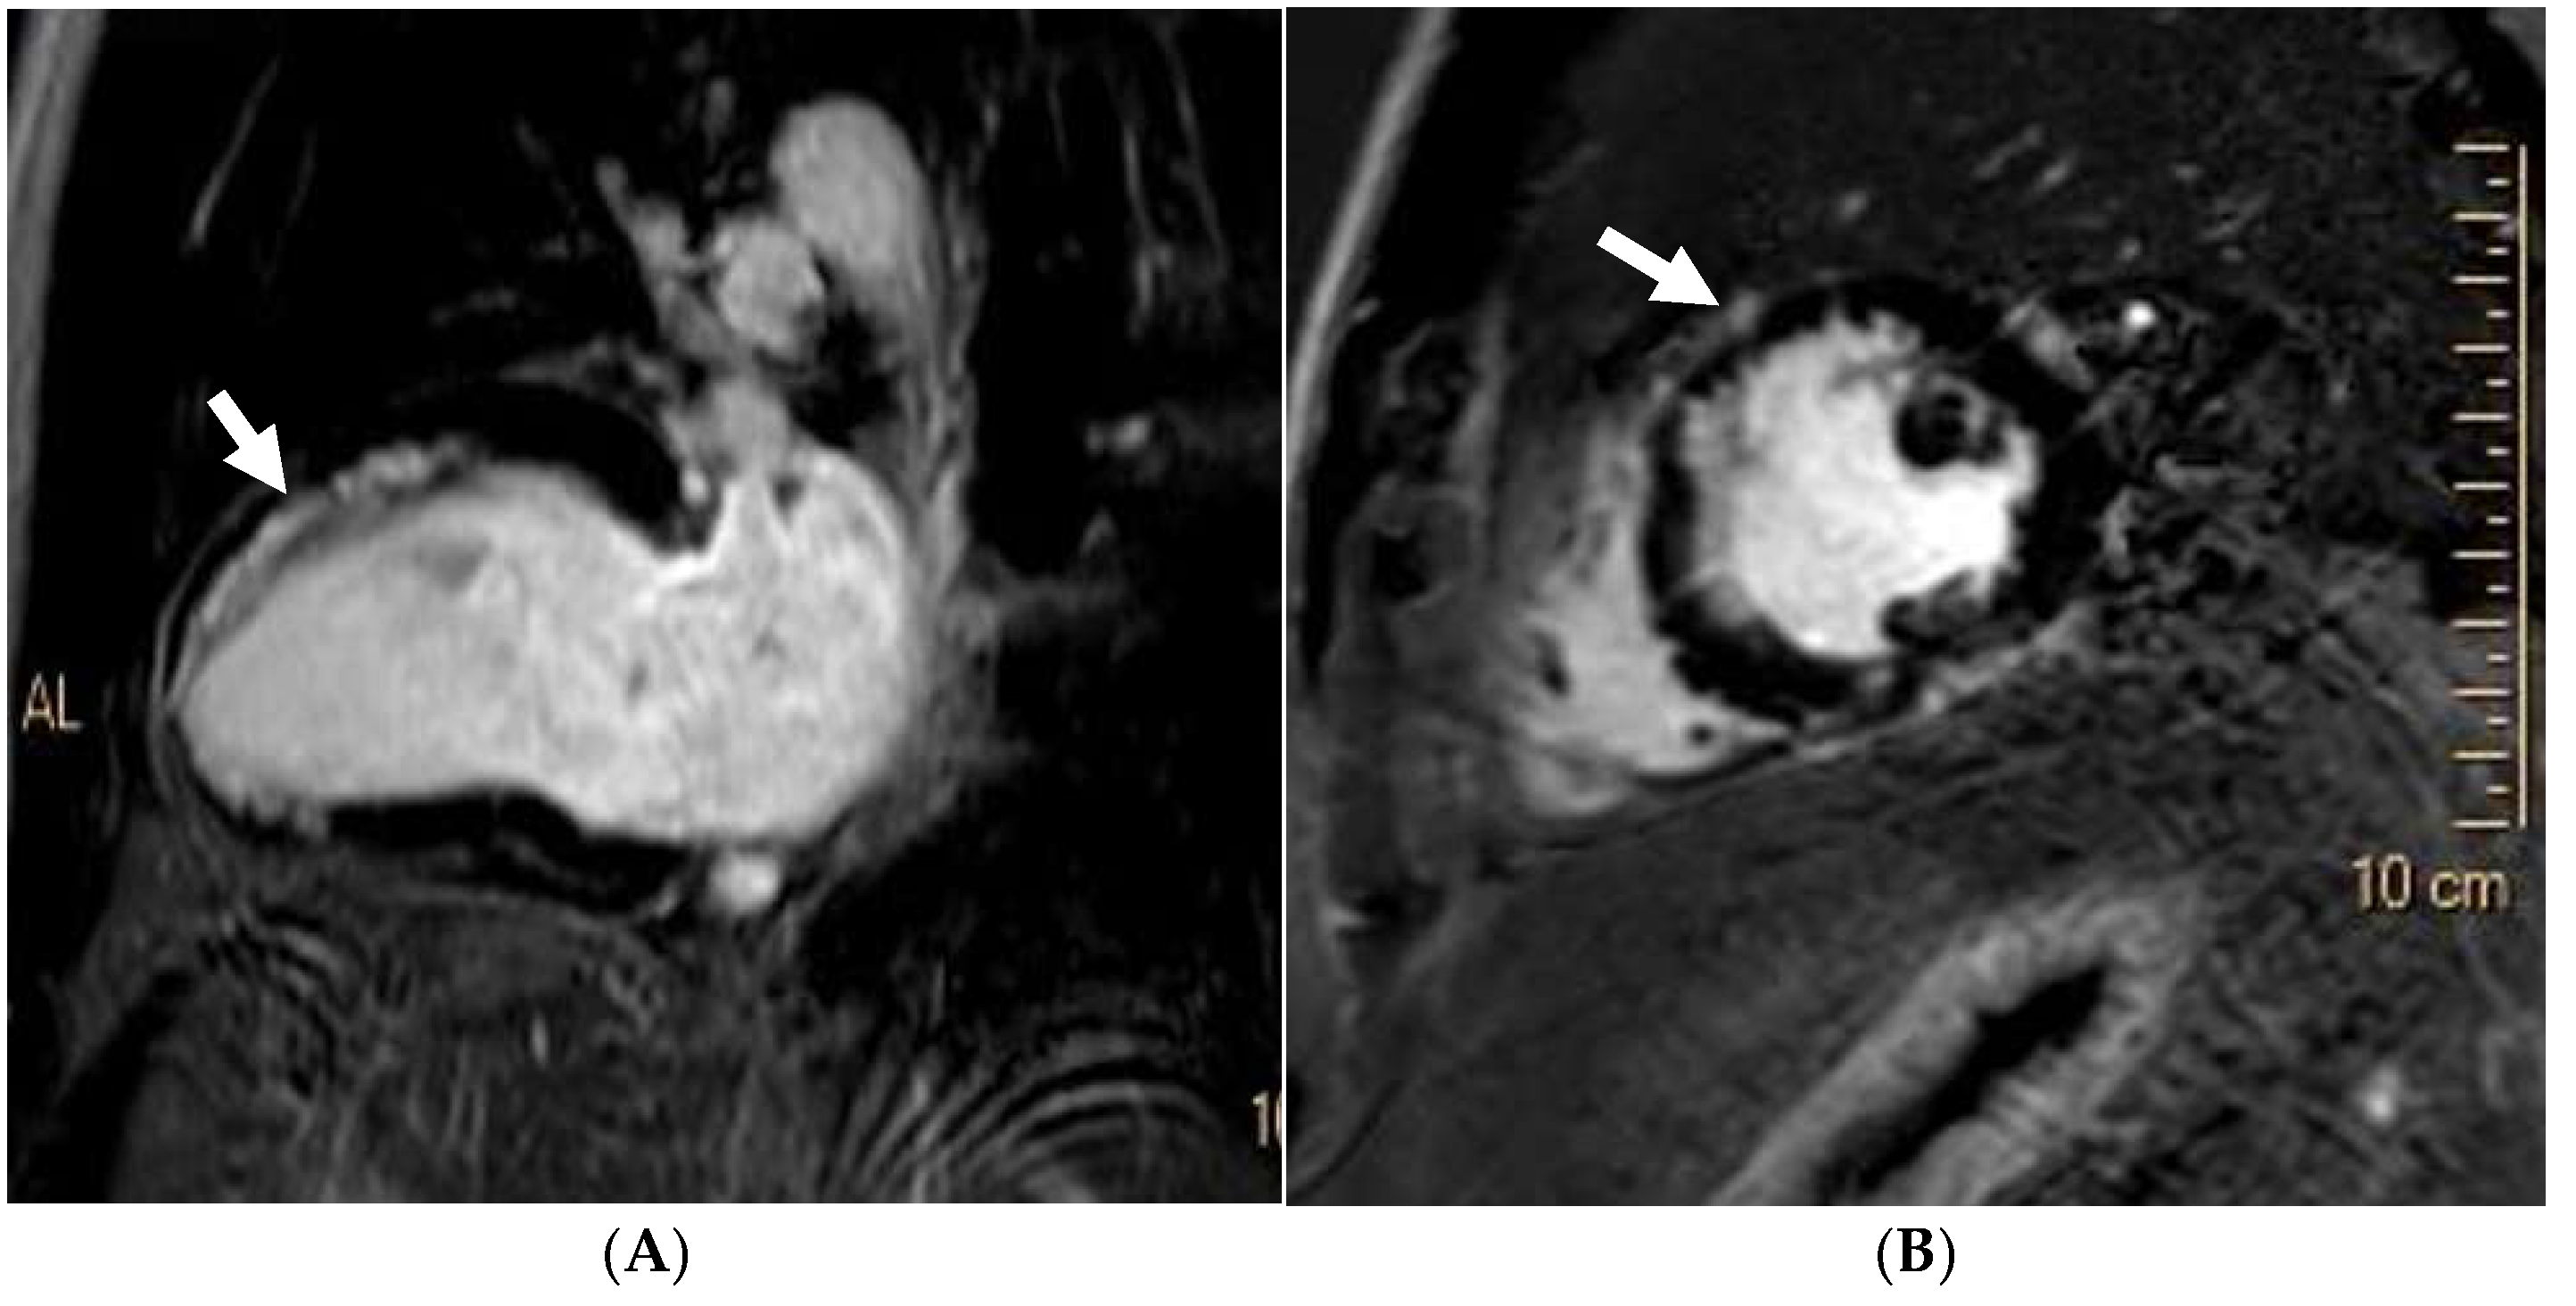

12. Mitral Valve Prolapse